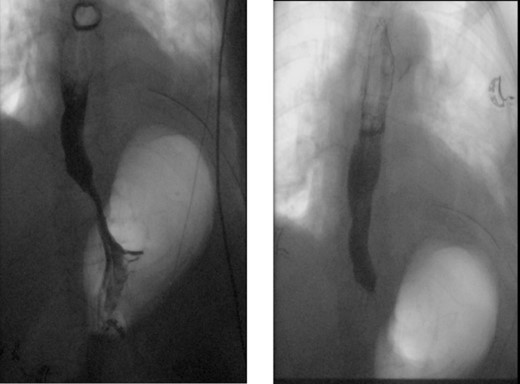

A 72-year-old woman with a past medical history of coronary artery disease and chronic gastroesophageal reflux disease (GERD) with hiatal hernia status postsurgical correction by Nissen’s fundoplication 20 years ago, presented with worsening episodes of intermittent dysphagia, heartburn, and postprandial cough of ~2 years duration but worsening symptoms over the past 2 months. She denies any symptoms of food regurgitation, nausea, vomiting, appetite, or weight changes. Upon her initial clinic evaluation, she had normal vital signs and unremarkable findings on the physical exam. The decision was made to start her empirically on a proton pump inhibitor, assuming her symptoms are related to GERD, to which she did not respond appropriately. A subsequent upper endoscopy revealed a large epiphrenic wide-mouthed ED (Fig. 1). Additionally, an esophagram showed a 6.0 × 5.0 cm epiphrenic ED with a 3.3 cm neck (Fig. 2). High-resolution esophageal manometry (HREM) was performed; thereafter, revealing a normal motility pattern (Fig. 3). She was then referred to cardiothoracic surgery for consideration of surgical repair. She was initially advised to follow a dysphagia-specific diet and wait conservatively on her symptoms, but no changes were observed in her clinical course over 6 months. The patient subsequently underwent a successful uncomplicated esophageal diverticulectomy with myotomy, conducted through a lateral thoracotomy. During surgery, an esophagogastroduodenoscopy (EGD) revealed an ED at 35 cm in the gastroesophageal (GE) junction at 40 cm in the epiphrenic region. A standard posterior lateral thoracotomy was performed in the serratus-sparing fashion, and the pleural space was entered at the seventh intercostal space. The esophagus was encircled with a Penrose drain lifting it up, and it was freed from the periaortic tissue, and the ED cleared off all muscle fibers. The diverticulum was excised from the esophagus using a purple load stapler with an EGD scope in place to prevent esophageal narrowing. A myotomy was performed from the GE junction proximally, with negative leak testing. The muscle layer was then imbricated over the area of diverticulectomy, and a chest tube was inserted for drainage. A postoperative esophagram confirmed no presence of an ED (Fig. 4). Immediately after the surgery, the patient had a complete resolution of her symptoms, and during her 1-year follow-up visit, she remained asymptomatic.

X-ray esophagram fluoroscopy showing a 6.0 × 5.0 cm epiphrenic ED with a 3.3 cm neck.